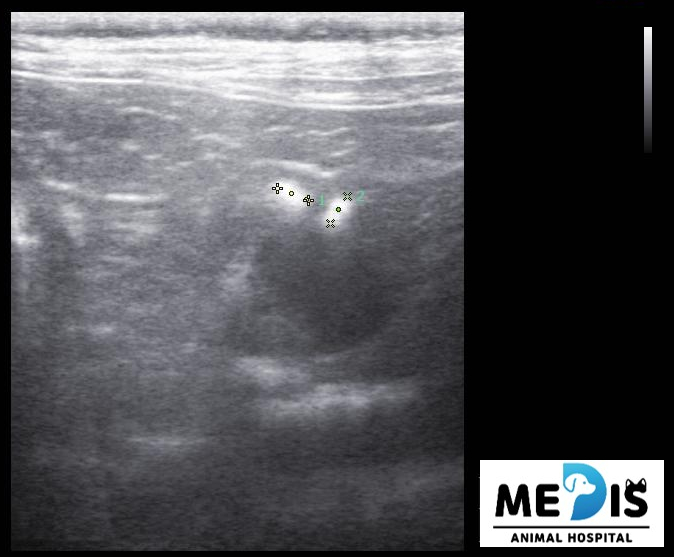

초음파에서도 담낭 주변이나 간 내부의 담도에 결석으로 의심되는 음영이 다수 관찰됐습니다.